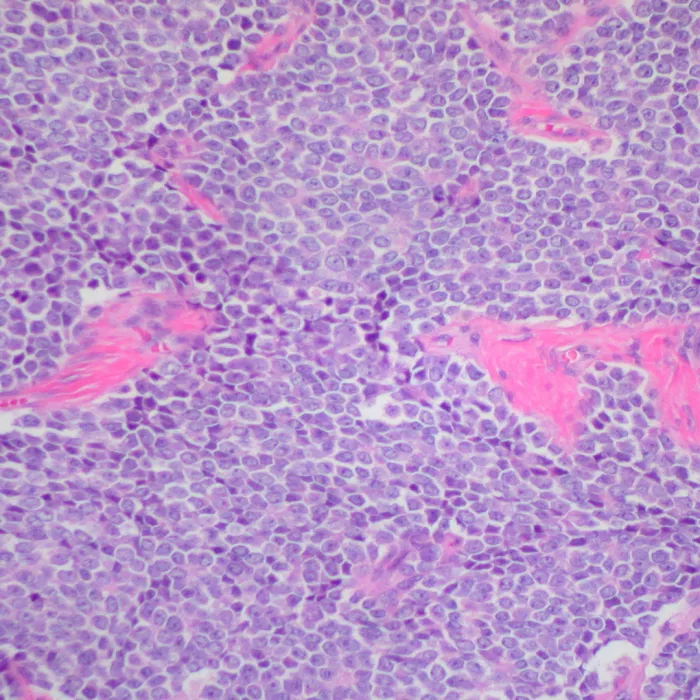

Tessuti tumorali

Attraverso un percorso fatto di immagini istologiche reali raccolte da ricercatori e medici durante il proprio lavoro, il pubblico vivrà un’esperienza che invita a scoprire, con uno sguardo nuovo, la complessità della malattia tumorale e il valore della ricerca scientifica.